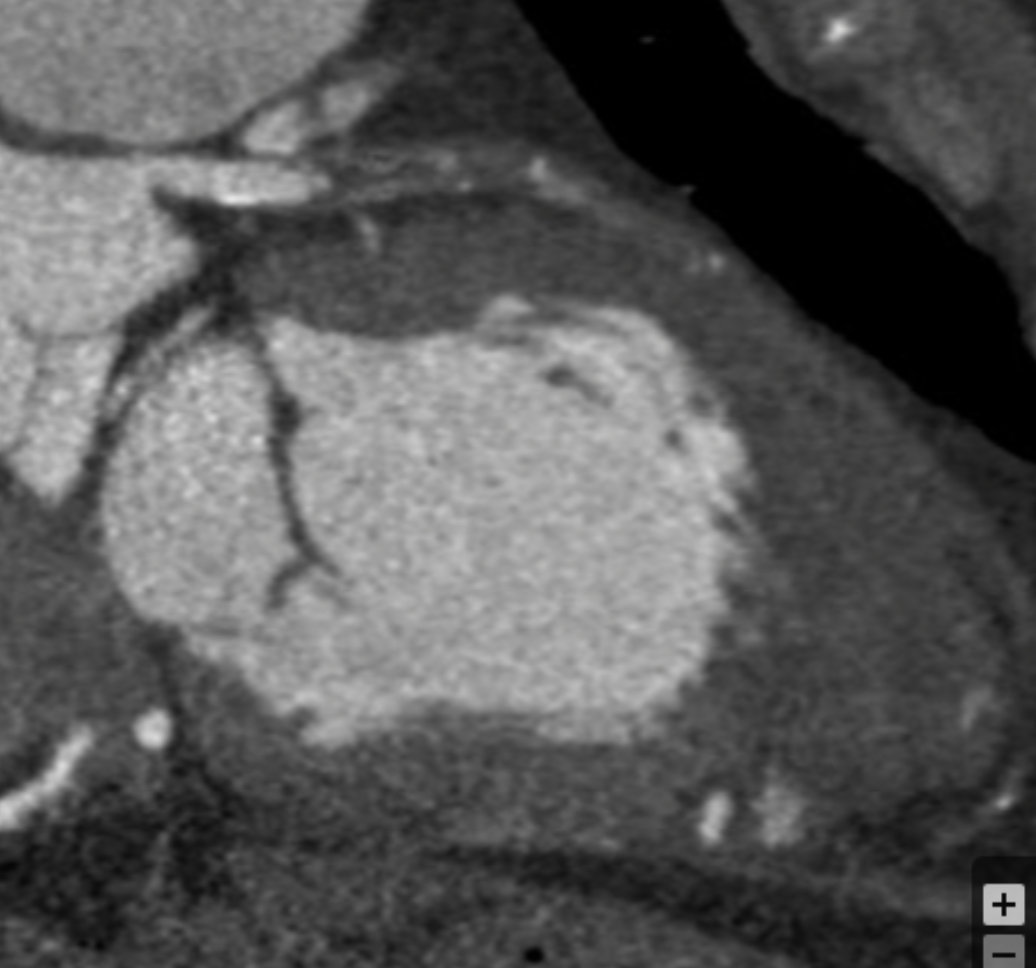

Describe the CT scan protocol/view:

Oblique MIP of the RCA

Describe the RCA findings in this image:

Cardiac Motion Artifact